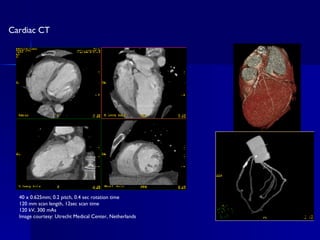

40 x 0.625mm; 0.2 pitch, 0.4 sec rotation time 120 mm scan length, 12sec scan time 120 kV, 300 mAs Image courtesy: Utrecht Medical Center, Netherlands Cardiac CT